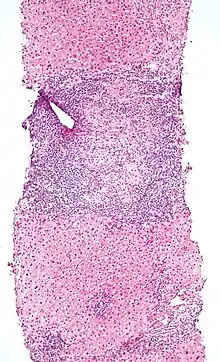

Micrograph of PBC showing bile duct inflammation and injury, H&E stain

On microscopic examination of liver biopsy specimens, PBC is characterized by chronic, nonsuppurative inflammation, which surrounds and destroys interlobular and septal bile ducts. These histopathologic findings in primary biliary cholangitis include:[32]

The Ludwig and Scheuer scoring systems have historically been used to stratify four stages of PBC, with stage 4 indicating the presence of cirrhosis. In the new system of Nakanuma, the stage of disease is based on fibrosis, bile duct loss, and features of cholestasis, i.e. deposition of orcein-positive granules, whereas the grade of necroinflammatory activity is based on cholangitis and interface hepatitis. The accumulation of orcein-positive granules occurs evenly across the PBC liver, which means that staging using the Nakanuma system is more reliable regarding sampling variability.

Histopathology stages (by Ludwig and Scheuer systems)

• Stage 1 – portal stage: Normal-sized triads, portal inflammation, subtle bile duct damage: Granulomas are often detected in this stage.

• Stage 2 – periportal stage: Enlarged triads, periportal fibrosis and/or inflammation, typically characterized by the finding of a proliferation of small bile ducts

• Stage 3 – septal stage: Active and/or passive fibrous septa

• Stage 4 – biliary cirrhosis: Nodules present, garland or jigsaw puzzle pattern